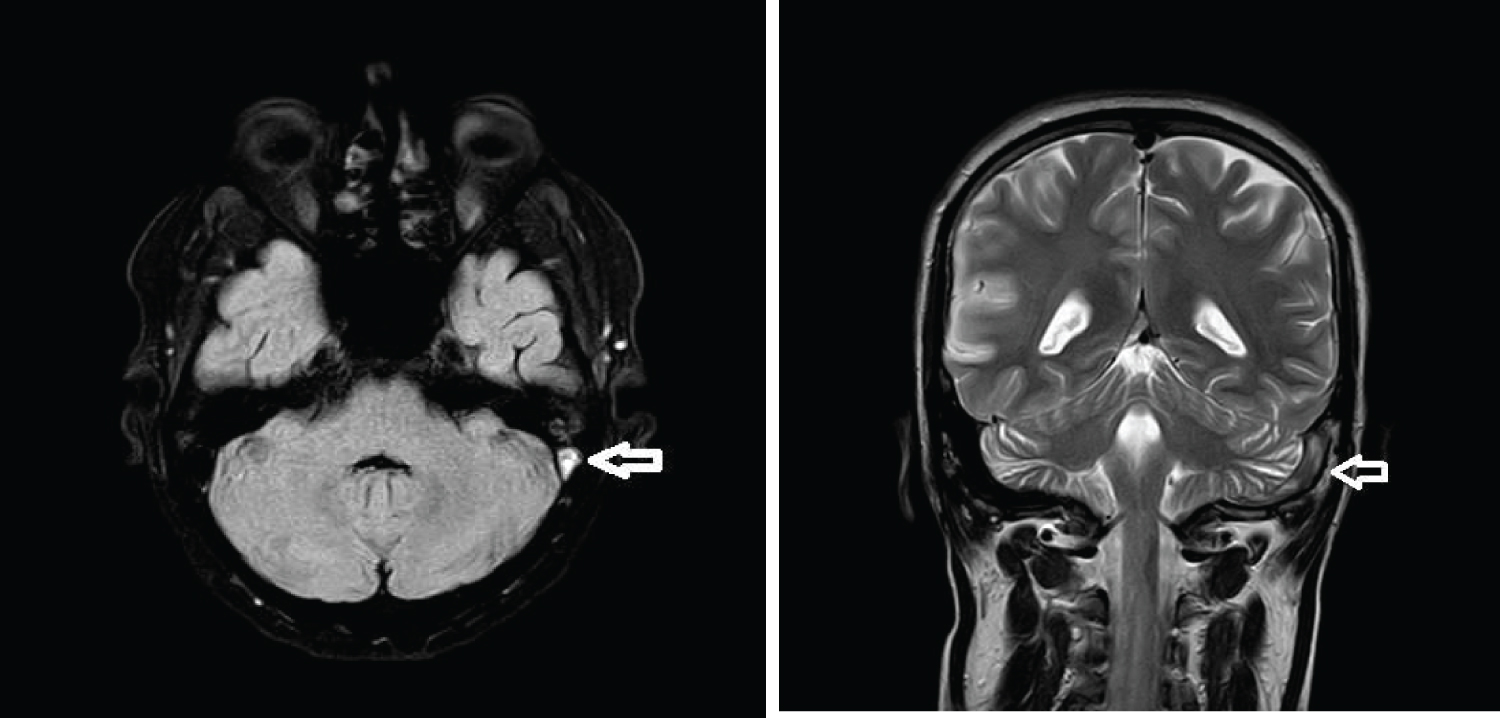

A routine follow up MRI brain done on day 13 post stroke showed that blooming in the right basal ganglia had reduced and there was considerable reduction in edema and no midline shift, however he was noted to have thrombosis of the left transverse sinus, left sigmoid sinus and proximal part of the left internal jugular vein. He was asymptomatic with no headache and improving clinically at this time (Figure 5 and Figure 6).

Figure 6: FLAIR axial and T2 coronal sequence show left transverse sinus thrombosis. View Figure Chart 6